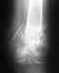

Неудачно сросшийся засарелый перелом пяточной кости

в 2008 году была травма - осколочный перелом пяточной кости правой ноги со смещением. До сих пор нога в области пятки опухает и болит. что делать?

Врач, к которому я обращался, говорит, что так должно быть, ведь перелом сложный. Но вот уже пятый год пошел - а сил терпеть нет. Я понимаю, что теперь моя травма нуждается в операции. подскажите, что делать и к кому обратиться. с уважением, дмитрий.